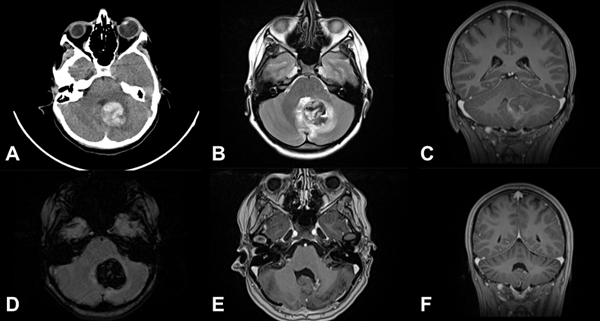

Figura 1. Tres casos de cavernomas cerebrales supratentoriales superficiales operados. A) y B) Imágenes prequirúrgicas y postquirúrgicas del paciente número 3: femenina de 7 años, que consulta por crisis parcial motora en miembro inferior derecho y crisis de ausencias. Secuencia SWI hipointensa correspondiente a restos hemáticos, secuencia T1 con contraste EV libre de lesión. C) y D) Imágenes pre y postquirúrgicas del paciente número 6: masculino de 2 años que es derivado por estatus convulsivo. TC de cerebro sin contraste que muestra extensa lesión parietotemporal derecha espontáneamente hiperdensa, con desvío de línea media y adelgazamiento de calota craneana homolateral. RM de cerebro con contraste EV, se observa cavidad porencefálica postoperatoria, recuperación de anatomía ventricular. E) y F) Imágenes pre y postquirúrgicas del paciente número 1: masculino de 12 años que consulta por crisis parciales simples motoras, que posteriormente generalizan. RM de cerebro con contraste EV que muestra lesión hiperintensa en región frontoopercular derecha. RM de cerebro con contraste EV postoperatoria, exéresis completa.

Las MC se localizan en el compartimento supratentorial entre el 60-90 %,1,3,9,17,24 y en nuestra serie fue del 61% (ver Figura 1). Acciarri y cols. encontraron predominio por el lado izquierdo en casos sintomáticos, mientras que nosotros no tuvimos predisposición por ningún lado.3 De nuestra serie, el 8% tuvo diagnóstico incidental, un porcentaje bajo e incluso menor a lo reportado por Bigi y cols. con un 14.2%.9